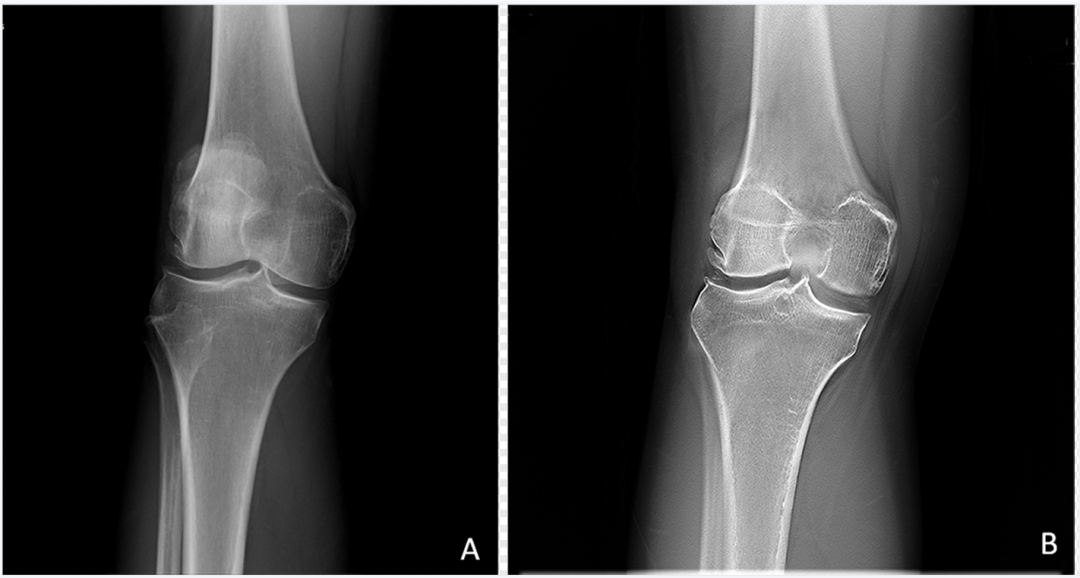

数字断层融合成像

在预设的融合体层曝光程序控制下,X线管组件完成多角度多次脉冲式曝光,结合位移叠加算法等数字化重建方法,创建检查区域内不同体层深度的聚焦层面图像。其中每幅图像的起始高度、层厚、层间距可以人为进行调整。DTS弥补了DR三维结构投影重叠的不足,空间分辨率高,相对于CT辐射剂量低。可清晰地显示骨折线,提高对隐匿性骨折的检出率和准确率(图1、图2)。

dr数字怎么用数字化X线摄影术(DR)_https://www.jmylbn.com_新闻资讯_第3张

图1  正常膝关节常规DR与DTS

A.常规DR;B.DTS